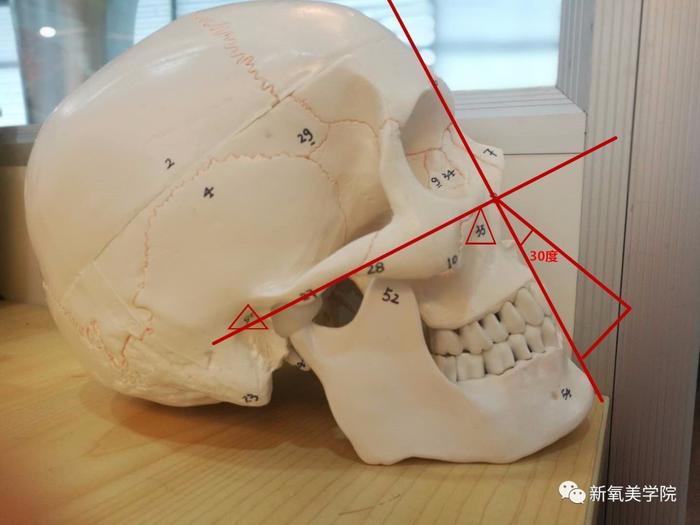

将一个人耳孔(下图数字25,标三角的位置)和眶下孔(下图数字35)划直线,再垂直方向划竖线,和牙龈形成的角度不超过30度,就是比较显年轻可爱的三分龅。